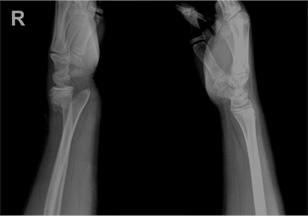

소아 손목 골절 수술 전

x-ray 사진

소아 손목 골절 수술 후